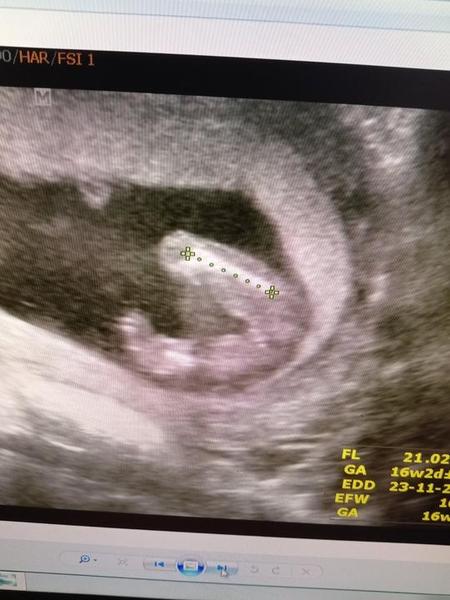

chtěla bych se s vámi poradit, co si myslíte, že čekáme 🙂, určitě máte některé zkušenější oko než my a jelikož jsme od doktorů slyšely obě varianty, ráda se poradím i s vámi, určitě jste takových obrázků už viděly spoustu 🙂. Přikládám foto z UTZ ve 20.týdnu. Moc děkuji!

Taky vidim holcicku

U fotky ze spodu to.jde poznat asi lépe než ze předu. Hold si budu muset počkat do 2. screeningu 😐

Holčička😊 krásná buchta tam je